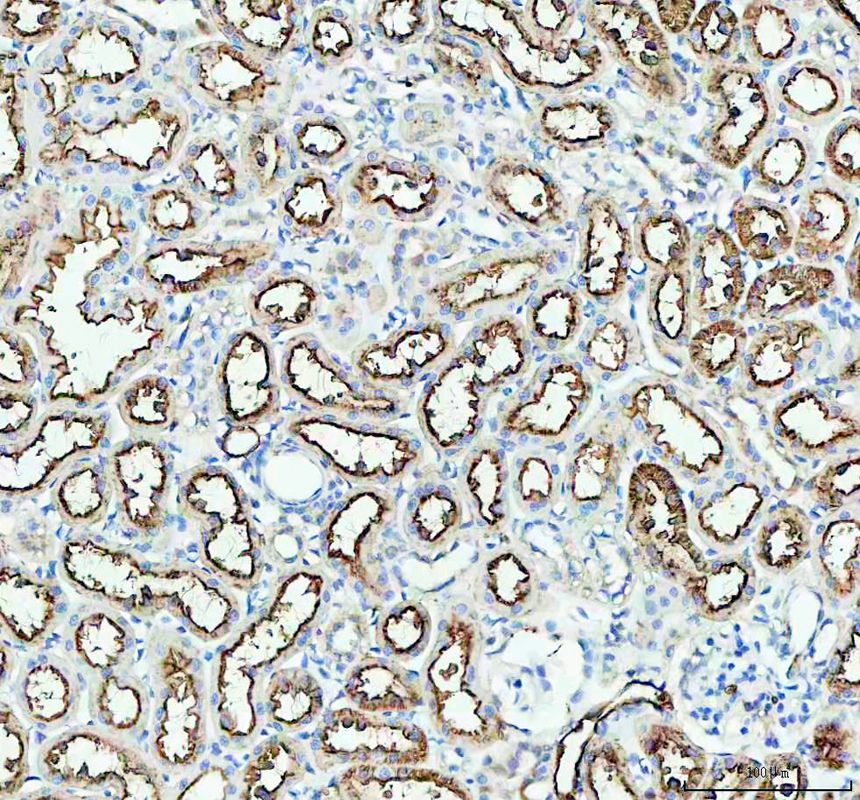

IHC analysis of AQP1 using anti-AQP1 antibody (PB9473).

AQP1 was detected in a paraffin-embedded section of rat kidney tissue. The tissue section was incubated with rabbit anti-AQP1 Antibody (PB9473) at a dilution of 1:200 and developed using HRP Conjugated Rabbit IgG Super Vision Assay Kit (Catalog # SV0002) with DAB (Catalog # AR1027) as the chromogen.